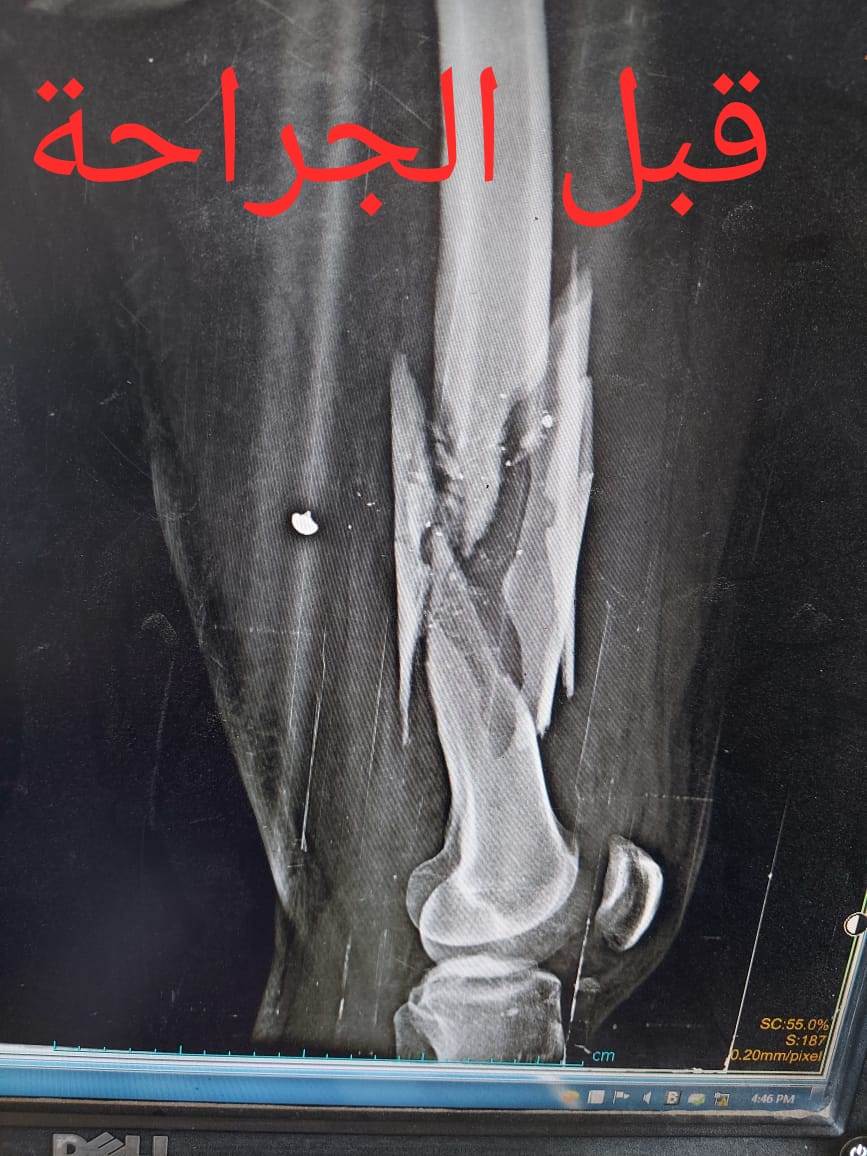

أعلن الدكتور سعد مكي، وكيل وزارة الصحة بالدقهلية، نجاح فريق طبي بمستشفى شربين المركزي، في إنقاذ شاب مصاب بكسر متفتت بالفخذ إثر بطلق ناري.

حيث تم إجراء تدخل جراحي دقيق لشاب يعاني من كسر مضاعف من الدرجة الثالثة، إثر طلق ناري، أدى إلى تهتك بالأنسجة، وكسور متفتتة بالفخذ، وذلك عن طريق جهاز "الليزاروف"، وتعد واحدة من عمليات العظام الكبرى والمتقدمة ذات المهارة الخاصة.